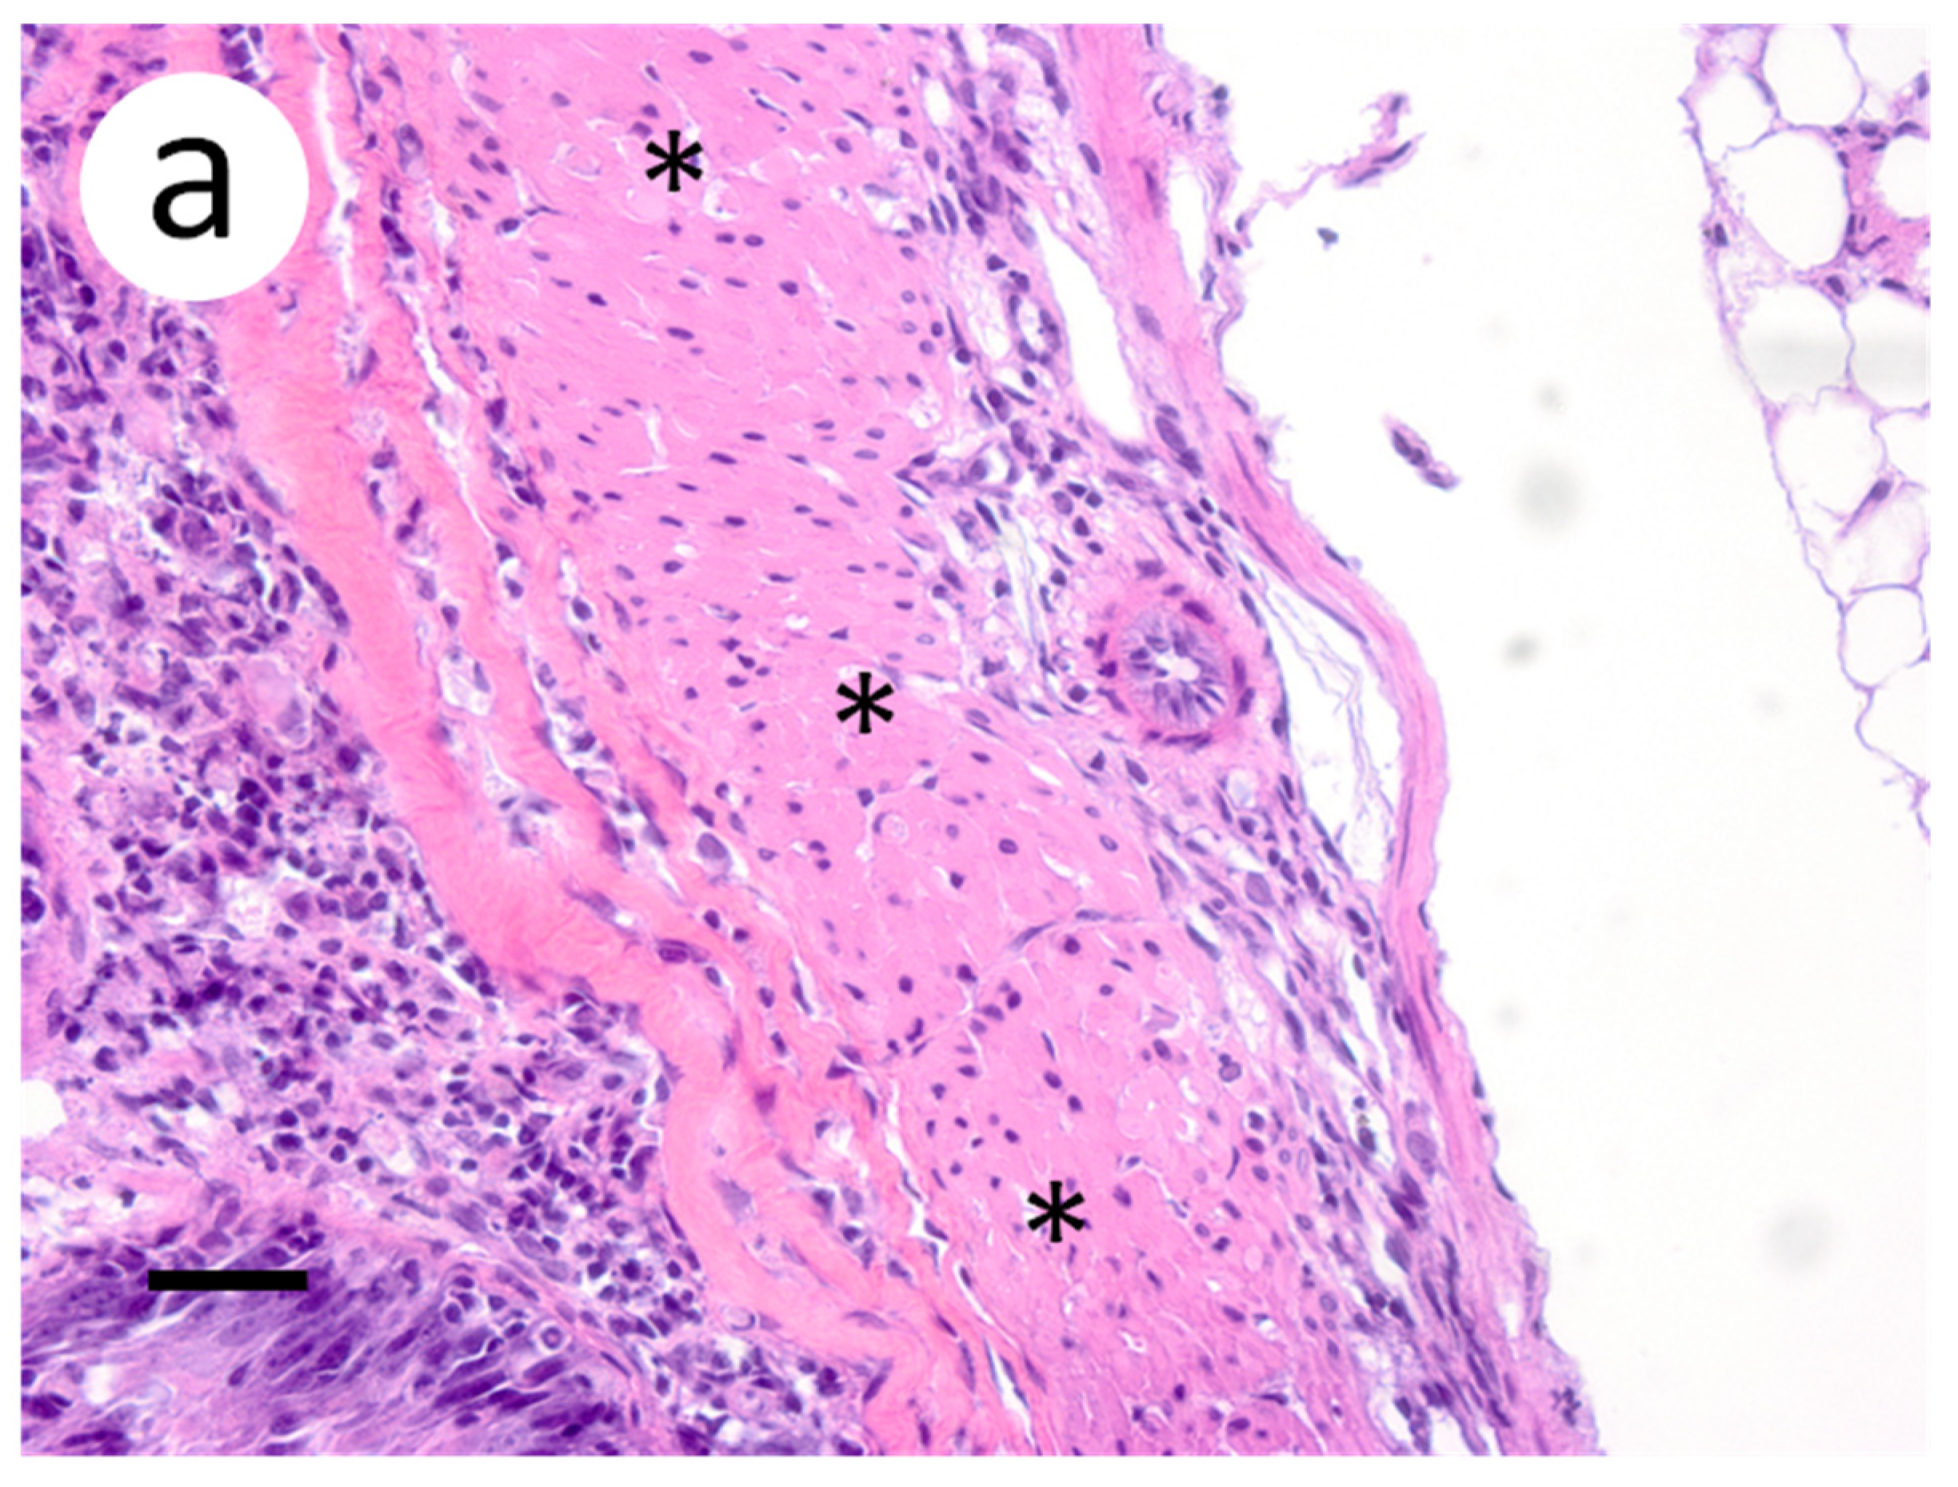

3.3. Visualization of VHSV-IVb in Tissues of Infected Muskellunge